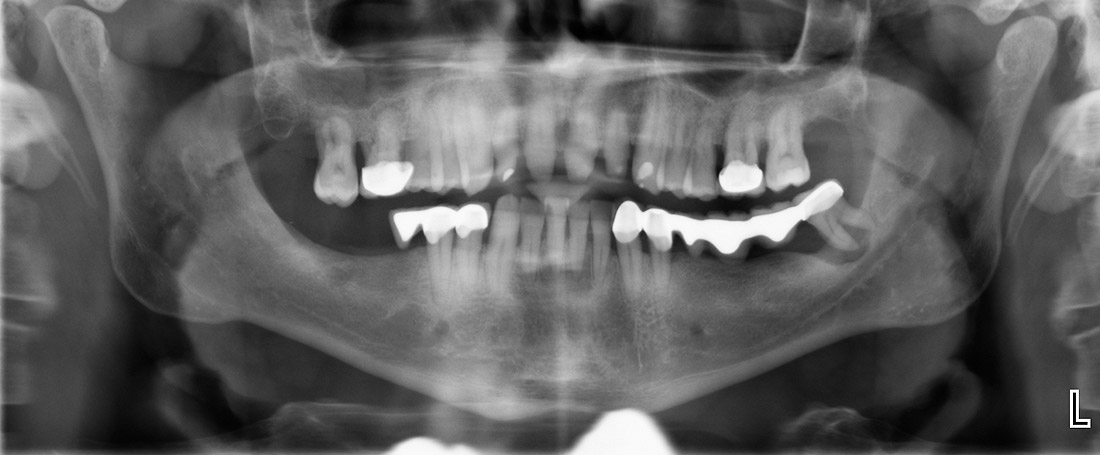

Zahnersatz

Wir kennen das alle: Implantate sind für viele ein großes Fragezeichen. Gut, wenn man dann einen erfahrenen Zahnarzt zur Seite hat, der schon viele Patienten zu strahlend neuen Zähnen gebracht hat.

Implantologie

Implantate sind seit etwa 40 Jahren in zahnärztlichem Gebrauch und haben sich bewährt: Mindestens 95 Prozent, das zeigten Studien, halten länger als fünf Jahre. Zurzeit werden allein in Deutschland jährlich knapp eine Million Implantate gesetzt.